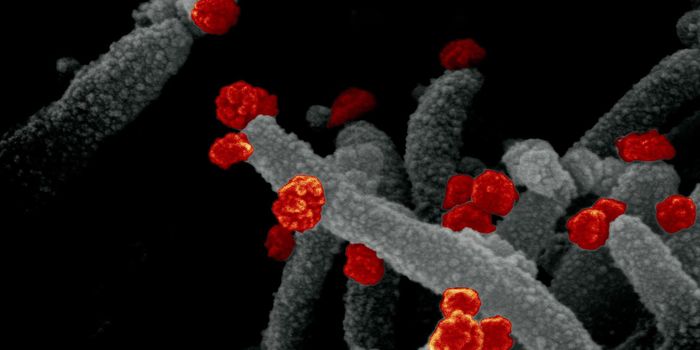

JUL 11, 2021MicrobiologyIn October 2020, what's now called the Delta variant of SARS-CoV-2 was first detected. It's now the most prevalent strai ...

NOV 01, 2021Cell & Molecular BiologyResearchers have learned a lot about the SARS-CoV-2 virus since the start of the COVID-19 pandemic. We know that he viru ...

SEP 07, 2021MicrobiologyThe world has rapidly become familiar with sarbecoviruses, two of which jumped to humans in recent years. The first was ...